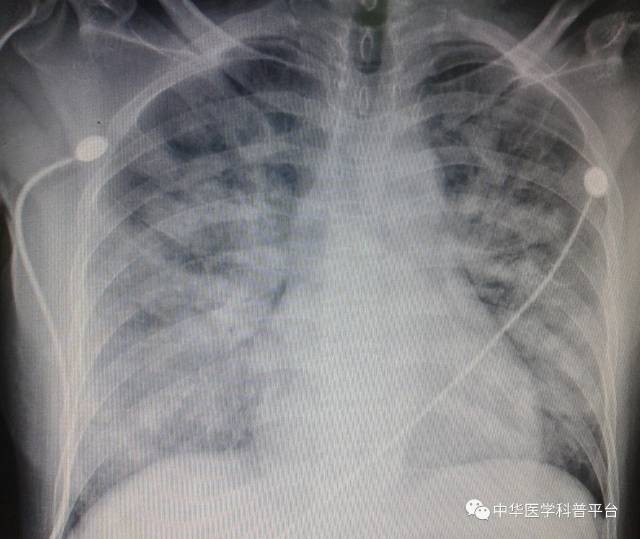

别走,您的肺炎"大发"了

射线照片也将被评估,以确定是否存在其他导致呼吸困难的原因,如肺炎

肺炎x光图片

肺炎胸片

轻度肺炎胸片